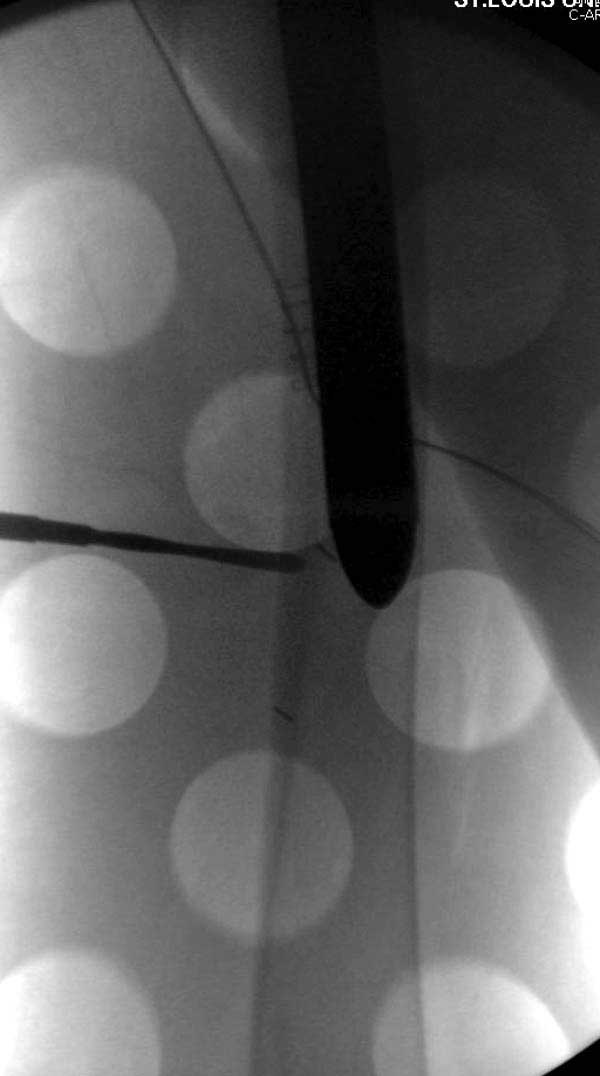

Такие “чужие осложнения” встречаются у всех и представляю банальный случай, который шаг за шагом показано как перерос в более сложный процесс... Больная 70 лет, множественные ко-морбидности, чрезвертельный перелом первоначально фиксирован Гамма 3. Осложнение в течение 6 недель, ревизия тотальной артропластикой и во время установки ножки обнаружена трещина диафиза (17), из малого доступа фиксация алло-графтом.

Повторно поступает после двух с половиной лет, где обнаруживается перелом на второй стороне. Немного сложно, но для фиксации выбрали Antegrade InterTan Smith Nephew Nail и с момента фиксации более 3х мес.